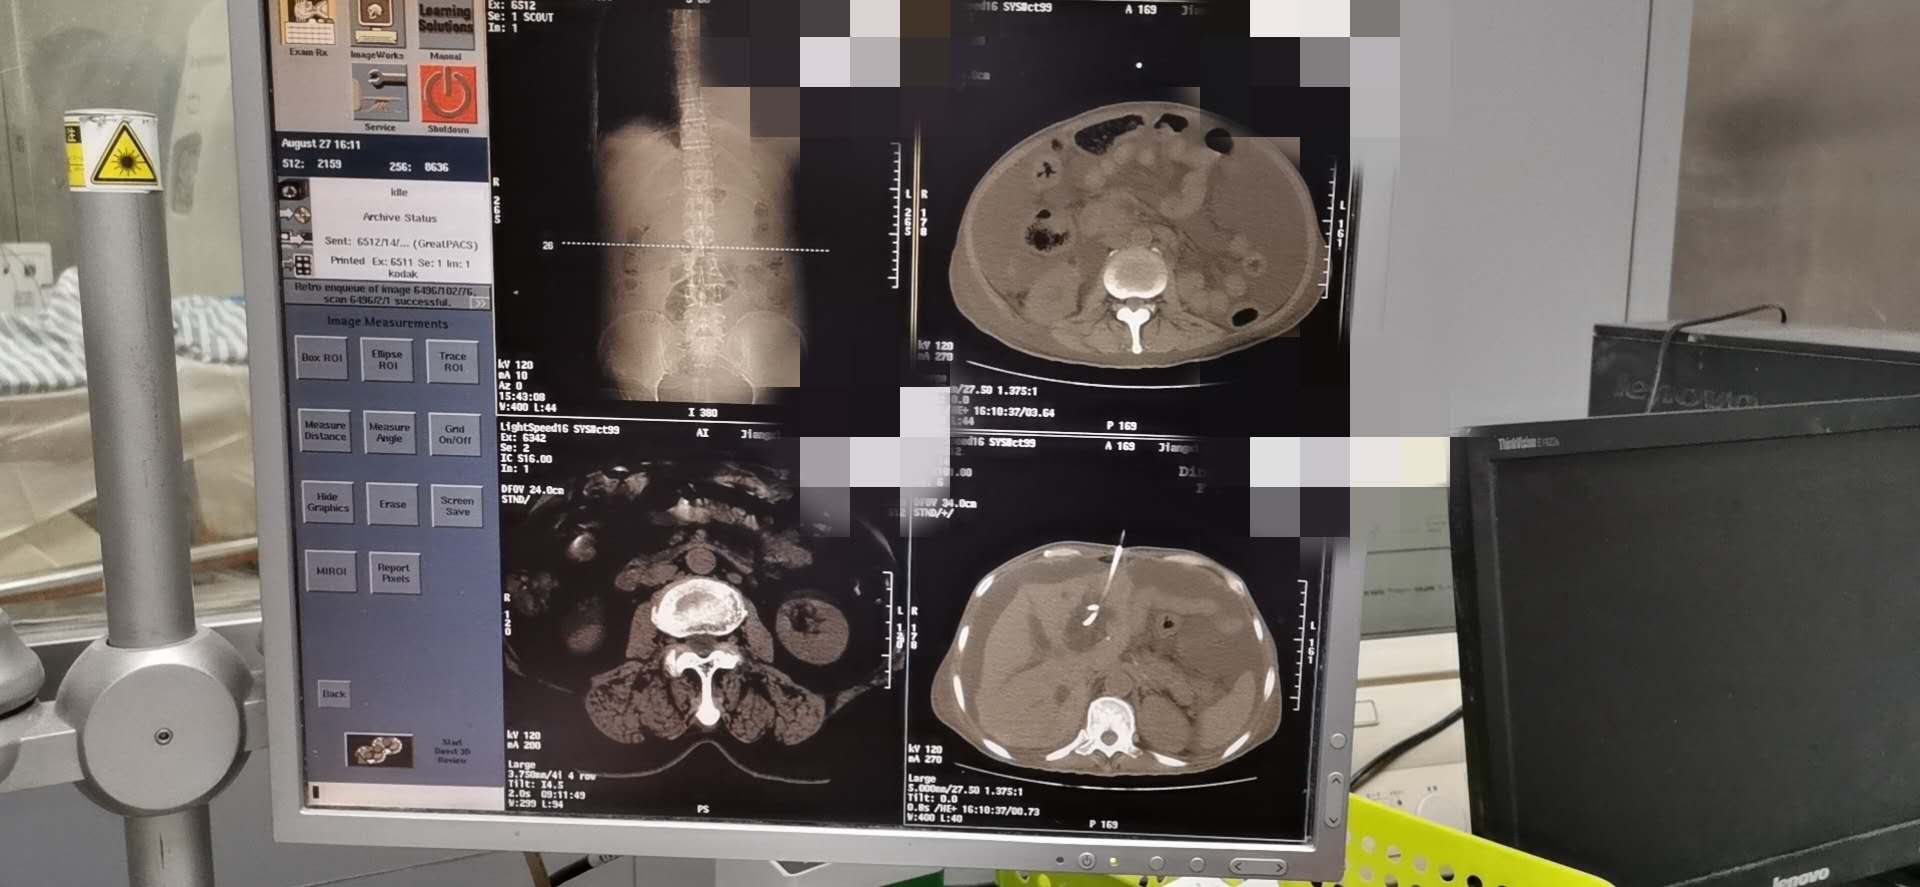

8.27肿瘤科于CT引导下行PTCD术

患者胃癌,肝门区转移瘤,导致阻塞性黄疸,如进一步恶化恐出现肝衰竭。于今日下午行PTCD术,希望能够为肿瘤治疗争取时机及延长患者生命。

通过不断学习、完善,科室可熟练、规范、全面地进行肿瘤的化疗、靶向、免疫等内科治疗。为了更好地诊断及治疗,科室开展了各种穿刺技术,包括胸腹水穿刺引流术、深静脉穿刺术、经皮穿刺肿瘤活检术及经皮穿刺肿瘤物理(射频/微波/冷冻)消融术及经皮肝穿刺胆道引流术等。